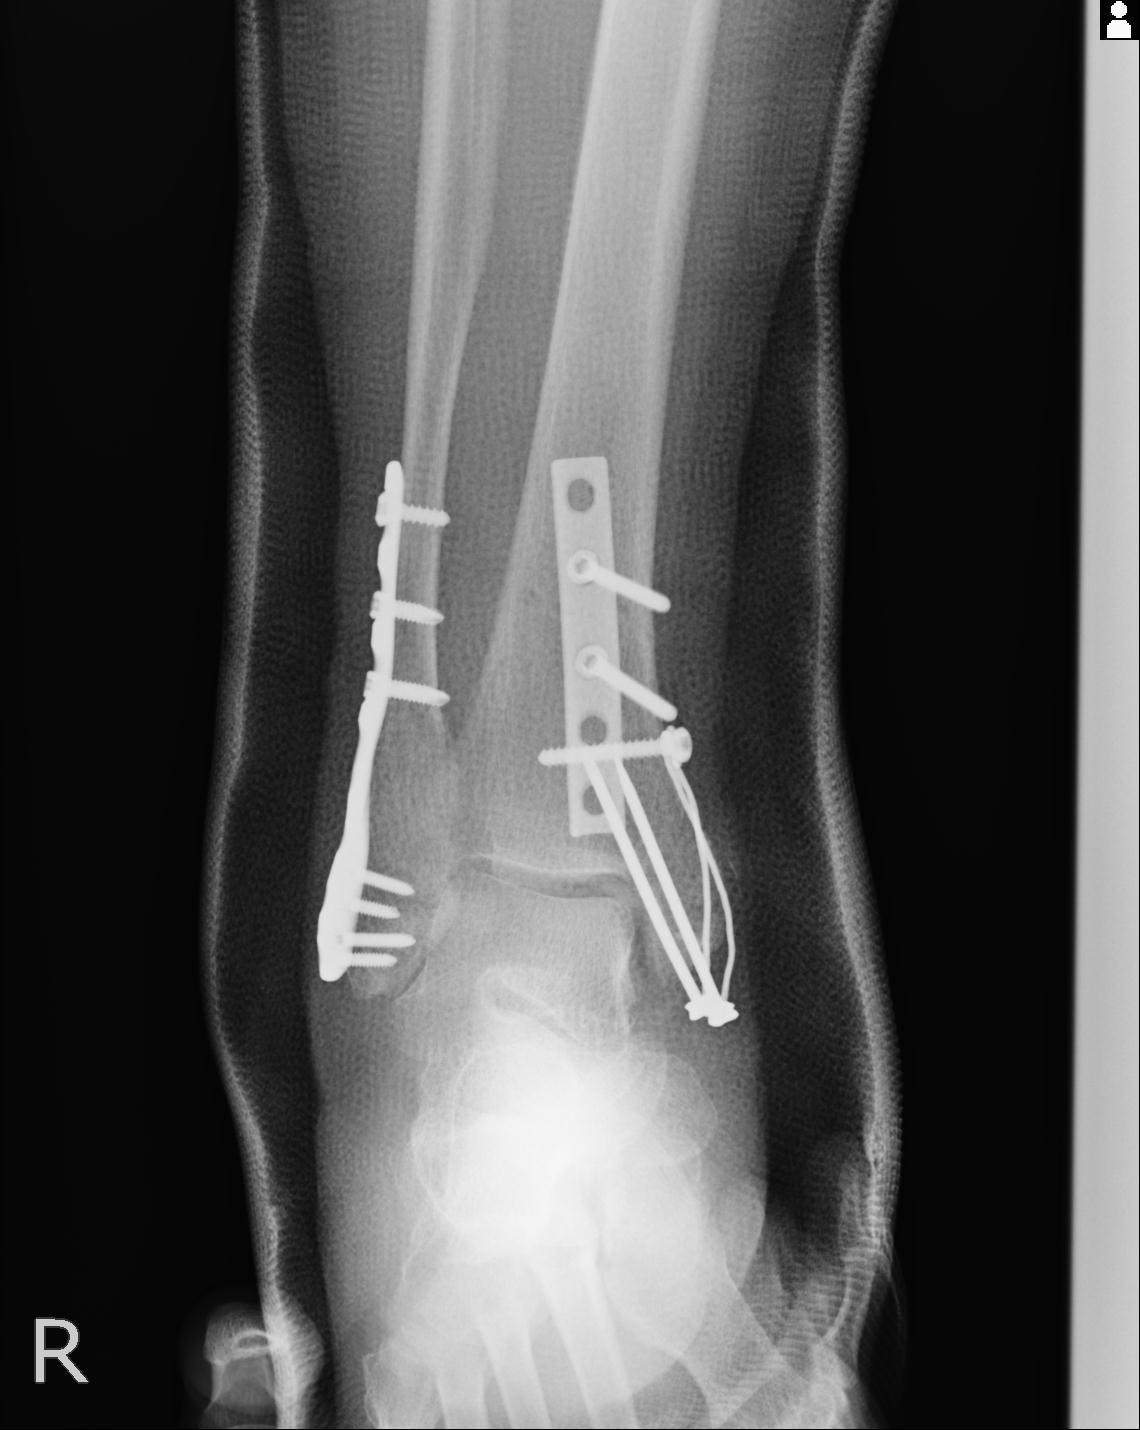

102755 1/4 2R 1/15 2R 右足関節 68歳女性 右三果脱臼骨折